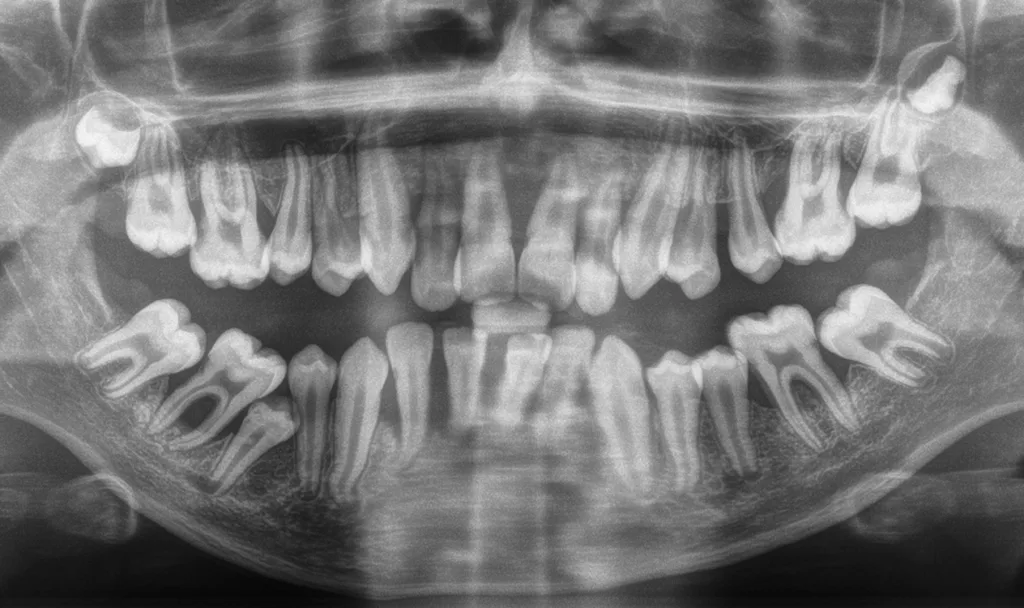

Primäre Immundefizienzen bilden die größte Gruppe an Syndromen, die sich mit einer Parodontitis manifestieren. Diese genetisch heterogenen Erkrankungen beeinträchtigen die Struktur, Reifung, Differenzierung oder Funktion von Organen und Zellen des Immunsystems. Sie werden typischerweise durch pathogene Veränderungen einzelner Gene – sogenannte monogene Mutationen – verursacht. Innerhalb dieser Gruppe sind insbesondere angeborene Störungen in Zahl und Funktion neutrophiler Granulozyten mit Parodontitis assoziiert. Typische Beispiele hierfür sind schwere kongenitale Neutropenien (Abb. 3, Abb. 4) und das Papillon-Lefèvre-Syndrom. Andere Syndrome, wie das Hermansky-Pudlak-Syndrom oder das Chediak-Higashi-Syndrom, resultieren aus Funktionsstörungen lysosomenassoziierter Organellen, die für die normale Aktivität zahlreicher Immunzellen essenziell sind, während wieder andere, wie die Leukozytenadhäsionsdefizienzen, durch eine defekte Leukozytenmigration bedingt sind. Im oralen Bereich führen primäre Immundefizienzen häufig zu rezidivierenden aphthösen Stomatitiden, rekurrentem Herpes, oropharyngealer Candidiasis, Ulzerationen und bakteriellen Infektionen. Diese Infektionen können wiederum eine früh einsetzende und rasch fortschreitende Gingivitis und in der Folge Parodontitis begünstigen.

Bei der zyklischen Neutropenie kommt es zu wiederkehrenden Abfällen der neutrophilen Granulozyten; typischerweise etwa alle 21 Tage. In diesen Phasen besteht eine erhöhte Infektanfälligkeit mit Symptomen wie Fieberschübe, Pharyngitis, Otitis media, Lymphadenitis sowie aphthoiden Läsionen der Mundschleimhaut. Zwischen den Zyklen ist das Blutbild meist normal, weshalb die systemische Diagnose durch Kinderärztinnen und -ärzte unter Umständen verzögert gestellt wird. Die Erkrankung wird überwiegend autosomal-dominant vererbt, weshalb häufig ein Elternteil betroffen ist, wobei die klinische Ausprägung variabel sein kann. Die Behandlung erfolgt häufig mit G-CSF, wodurch die Symptome deutlich reduziert werden können.